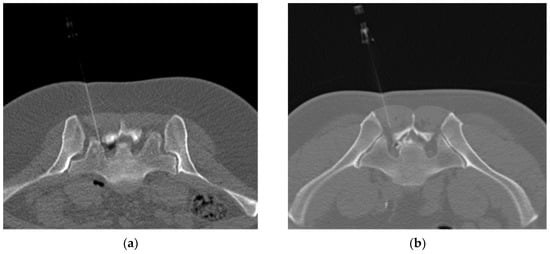

2.4. Interventions